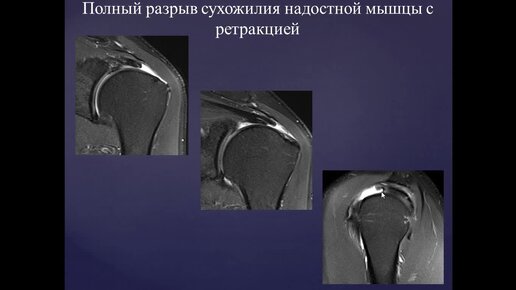

Базовый курс по МРТ- b. Лекция «МР-семиотика повреждений плечевого сустава». Лектор- Учеваткин А.А.